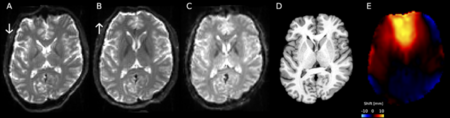

MRI スキャナーは、患者の体内の非常に小さな点を検出し、基本的に「あなたはどのような種類の組織ですか?」と尋ねることができます。このシステムは患者の身体を点ごとに調べて、組織タイプのマップを構築します。次に、このすべての情報を統合して、フーリエ変換として知られる数式を使用して 2-D 画像または 3-D モデルを作成します。コンピューターは、回転する陽子からの信号を数学的データとして受け取ります。データは画像に変換されます。それがMRIの「画像化」の部分です。

MRI システムでは、注入可能な造影剤、つまり色素を使用して、検査対象の組織内の局所的な磁場を変更します。正常な組織と異常な組織は、このわずかな変化に対して異なる反応を示し、異なる信号を私たちに与えます。これらの信号は画像に転送されます。 MRI システムは、さまざまな組織を描写するために 250 を超えるグレーの階調を表示できます 。この画像により、医師はコントラストを使用しない場合よりも、さまざまな種類の組織異常をより正確に視覚化できます。 「A」を実行すると、正常な組織は「B」のように見えることがわかっています。そうでない場合は、異常がある可能性があります。

X 線検査は医師に骨折を示すのに非常に効果的ですが、臓器、靭帯、循環器系を含む患者の軟組織を観察したい場合は、MRI が必要になる可能性があります。そして、最後のページで述べたように、MRI のもう 1 つの大きな利点は、任意の平面で画像を撮影できることです。たとえば、コンピュータ断層撮影 (CT) は、アキシャル面という 1 つの平面に限定されます (食パンに例えると、アキシャル面は通常の食パンのスライス方法となります)。 MRI システムは、患者が動くことなく、アキシャル画像だけでなく、矢状面(パンを縦に横にスライスした状態) および冠状面(レイヤーケーキの層を思い浮かべてください) 画像、またはその間の任意の角度の画像を作成できます。